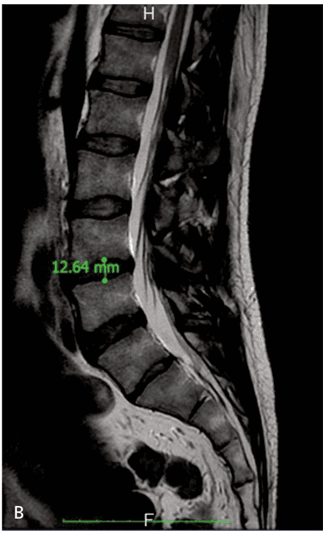

Low back pain treated with disc decompression and autologous microfragmented adipose tissue: a case report

P. Grossi, S. Giarratana, S. Cernei, S. Grossi, F.M. Doniselli, unknown, 2016

P. Grossi, S. Giarratana, S. Cernei, S. Grossi, F.M. Doniselli, 2016